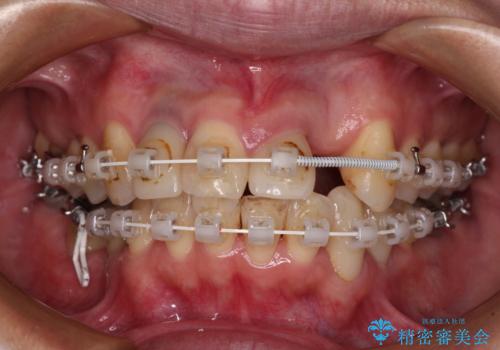

- 非対称な前歯や奥歯の目立つ銀歯を気にして来院された患者様です。

左上前から2番目の歯は、以前裏側に位置していたことから抜歯をされていましたが、前歯の非対称が長年気になっているとのことでした。

矯正治療によって前歯にスペースを作り、左右対称となるようにオールセラミッククラウンにて補綴治療を行うとしました。

他にも奥歯の咬み合わせに問題があったので、全顎的な矯正治療を行い、前歯以外にも口を開けたときに目立つ奥の銀歯をセラミッククラウンにて補綴治療を行うこととしました。